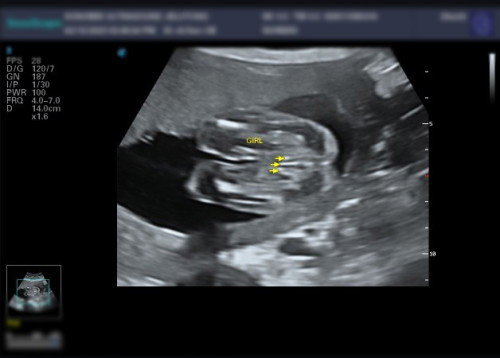

Gender bayi

Confirm ke girl..scan KK masih tak nmpak...detail.scan katanya girl...anak first boy..😇#seriusnanya #ingintahu

nmpk cm girl sbb 3 garis mcm sy jg scan hritu prut 5 bulan and confirm girl

Rasanya girl sis sebab nampak sangat mcm sign burger tu 🤭

girl sbb ada 3line